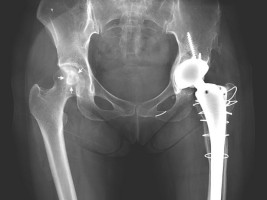

대퇴골두 무혈성 괴사의 진행 여부를 좌우하는 인자가 밝혀져 치료의 새로운 지침을 제시하는 연구 결과가 나왔다.

서울대병원 정형외과 김희중·유정준 교수팀은 증상이 없이 우연히 발견된 대퇴골두 무혈성 괴사 환자 105명을 최소 5년 이상(5-15년으로 평균 8년 7개월) 추적 관찰해 얻은 괴사의 자연적인 경과를 최근 발표했다.

특히, 괴사의 크기가 전체 대퇴골두의 30% 이하일 경우에는 거의 진행하지 않는 것으로 확인되어(5%만 진행), 작은 괴사의 경우 특별한 치료가 필요 없을 것으로 판단되었다. 또한, 거의 대부분의 괴사(94%)는 5년 이내에 진행 여부가 결정됨을 관찰했다.

정형외과 김희중교수는 “이번 연구를 통해, 30% 이하의 크기가 작은 괴사는 수술을 하지 않더라도 진행할 가능성이 거의 없어 작은 크기의 괴사에도 시행하던 불필요한 수술을 줄여줄 것으로 기대된다”며 “증상이 없는 괴사는 대부분 5년 이내에 진행할지 여부가 결정되므로 괴사 환자들의 추적 관찰에 중요한 지침으로 활용될 것으로 예측된다”고 말했다.